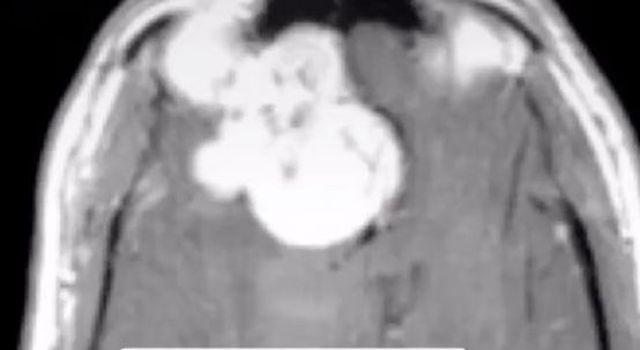

Однако буквально за несколько часов до судебного заседания обвиняемый был экстренно госпитализирован в реанимацию с сильными головными болями. Сканирование мозга показало наличие очень большой опухоли в правой орбитофронтальной коре.

"Эта зона контролирует социальное поведение. Врачи сказали, что именно эта опухоль вызвала у него симптомы сексуального влечения к детям. После того, как опухоль была удалена, все его позывы тут же прекратились", — рассказывает доктор Раджан.